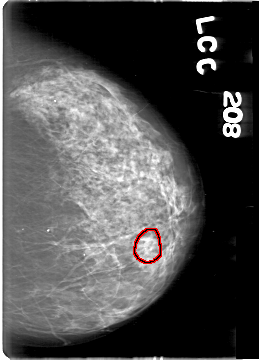

D_4164_1.LEFT_CC

LEFT_CC LINES 5386 PIXELS_PER_LINE 3871 BITS_PER_PIXEL 12 RESOLUTION 43.5 OVERLAY

FILE: D_4164_1.LEFT_CC.OVERLAY

TOTAL_ABNORMALITIES 1

ABNORMALITY 1

LESION_TYPE CALCIFICATION TYPE AMORPHOUS DISTRIBUTION CLUSTERED

ASSESSMENT 0

SUBTLETY 3

PATHOLOGY BENIGN

TOTAL_OUTLINES 1

BOUNDARY